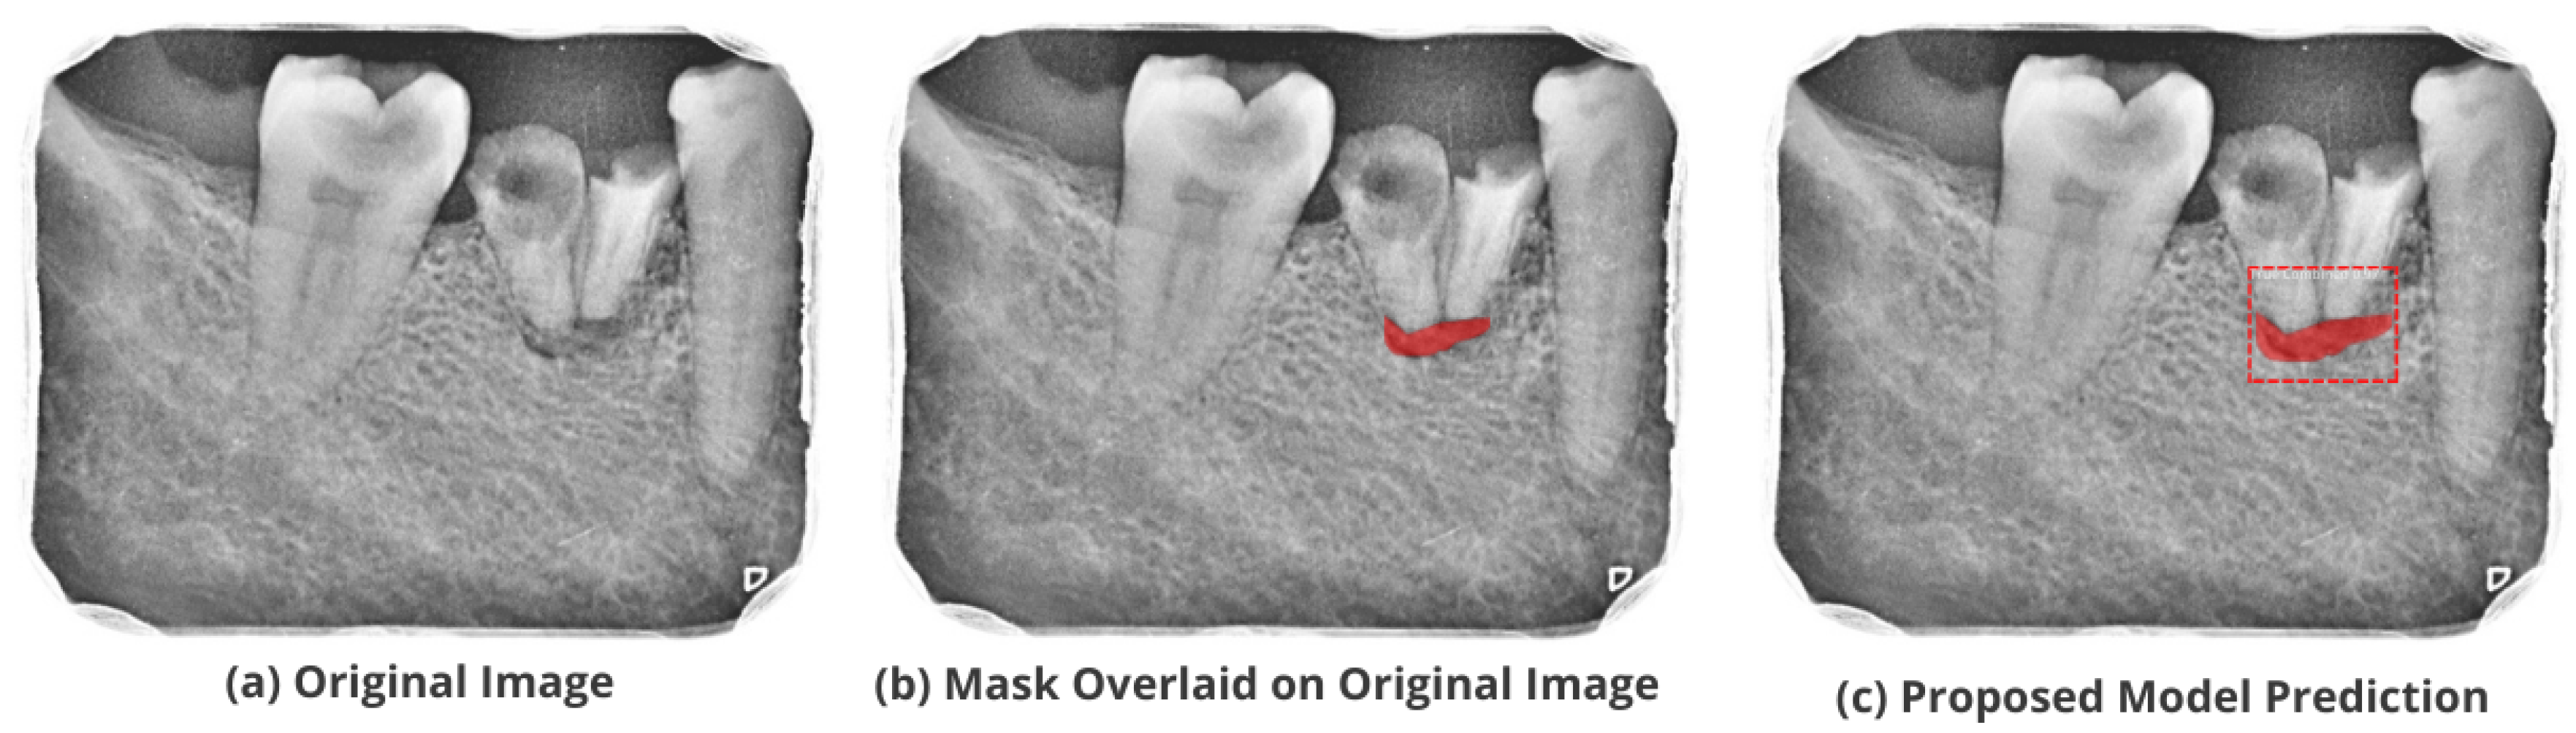

3.5. Comparison with Test Images

The proposed model accurately predicts and localizes the lesions as depicted in Figure 10, Figure 11, Figure 12, Figure 13 and Figure 14. The results indicate that the model makes predictions similar to that of the annotated masks using the periapical radiographic images. Additionally, the proposed model was evaluated based on performance indicators like precision, recall, F1 score, and accuracy for each classified periodontal lesion. The obtained results indicate that the proposed backbone network provides good performance for disease classification. All the test images for the proposed study show a 95% confidence level indicating that the database annotations are in the right direction.

Figure 12.

Test performance for the localization of a ’Primary Perio and Secondary Endo’ lesion.